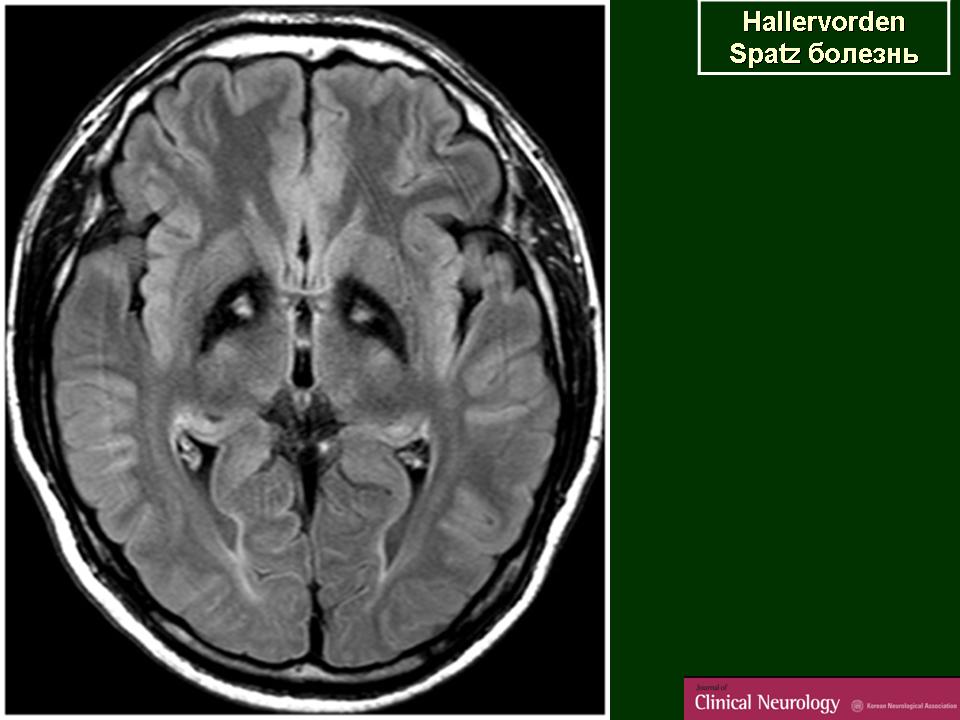

Болезнь Галлервордена - Шпатца - наследственное заболевание экстрапирамидной системы, связанная с нарушением обмена железа и липидов и повреждением бледного шара и черной субстанции. Тип наследования аутосомно-рецессивный. При патоморфологическом исследовании характерным признаком является гиперпигментация бледного шара и черной субстанции. Обнаруживается пигментация коры полушарий большого мозга и таламуса. Пигмент находится внутри невронов и глиальных клеток, расположенных около сосудов; содержит железо (вместе с тем каких-либо нарушений обмена железа в организме не обнаружено). Наблюдаются утолщение и фрагментация аксонцилиндров в пораженных областях. Постепенно наступает дегенерация невронов коры полушарий большого мозга и мозжечка. Характеризуются нарастающей экстрапирамидной ригидностью, гиперкинезами (атетоз, торсионная дистония), затем развивается акинетико-ригидный синдром, пирамидная микросимптоматика, снижение интеллекта. Течение медленно прогрессирующее на протяжении 10 - 20 лет.

"Глаз тигра"-наглядно и красиво.

Вы правы. Выставил еще более нагладные исллюстрации.